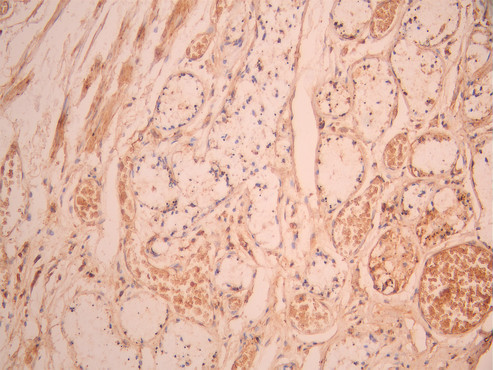

IHC image of CSB-RA004793MA1HU diluted at 1:50 and staining in paraffin-embedded human lung tissue performed on a Leica BondTM system. After dewaxing and hydration, antigen retrieval was mediated by high pressure in a citrate buffer (pH 6.0). Section was blocked with 10% normal goat serum 30min at RT. Then primary antibody (1% BSA) was incubated at 4°C overnight. The primary is detected by a Anti-Human lgG, Fcy Fragment Specific labeled by HRP and visualized using 0.05% DAB.